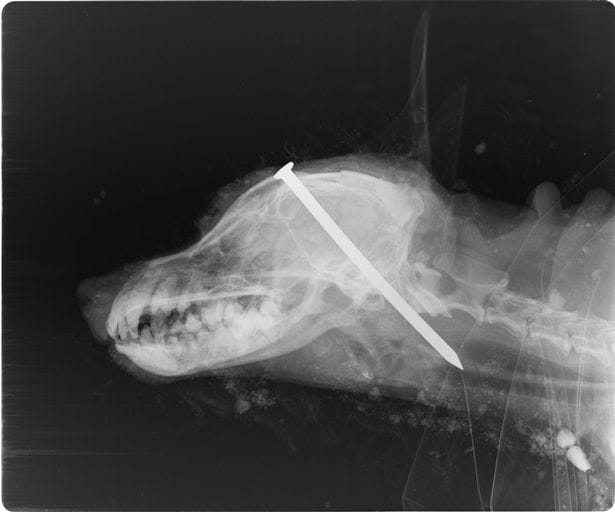

Michael Heathcock, âgé de 59 ans, affirme que son chien, Scamp, était aveugle et sourd. Il ajoute que l'animal peinait aussi à utiliser ses pattes arrière et qu'il était devenu incontinent. Face au coût élevé de l'euthanasie, Michael Heathcock, accompagné de Richard Finch, 60 ans, a décidé d'abréger lui-même les souffrances supposées de Scamp.Les deux hommes se sont emparés d'un marteau et de clous, puis ont emmené l'animal en pleine forêt, où Michael Heathcock lui a enfoncé un clou dans le crâne. Il a fallu six coups de marteau pour que la tige en métal transperce la tête de Scamp. Richard Finch, qui faisait le guet, a encouragé son ami à commettre ce crime atroce.

Scamp ne bougeait plus lorsque les deux hommes l'ont jeté dans un trou, persuadés que l'animal était mort.Le chien a cependant été secouru quelque temps plus tard par un couple en balade dans les bois. Encore en vie, Scamp implorait et gémissait sous le tas de terre recouvrant le trou où il avait été enterré.